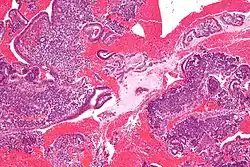

In histopathology, a small-blue-round-cell tumour (abbreviated SBRCT), also known as a small-round-blue-cell tumor (SRBCT) or a small-round-cell tumour (SRCT), is any one of a group of malignant neoplasms that have a characteristic appearance under the microscope, i.e. consisting of small round cells that stain blue on routine H&E stained sections.

These tumors are seen more often in children than in adults. They typically represent undifferentiated cells. The predominance of blue staining is because the cells consist predominantly of nucleus, thus they have scant cytoplasm.[1][2]